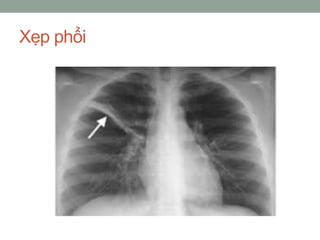

Xẹp phổi

4. Xẹp phổi do chèn ép phế quản.

• trường hợp tiến triển mạn tính, nhưng hạch to gây chèn

ép, hoặc xẹp một phân thuỳ phổi, chẩn đoán chủ yếu dựa

vào X-quang.

• Nếu xẹp phổi do tắc đột ngột một phế quản lớn như hít

phải một dị vật, cục máu chít phế quản sau khi ho ra máu,

triệu chứng đầu tiên là khó thở dữ dội, khám thực

thể thấy xuất hiện hội chứng ba giảm như trong tràn

dịch màng phổi, và di động lồng ngực bện xẹp kém rõ rệt.